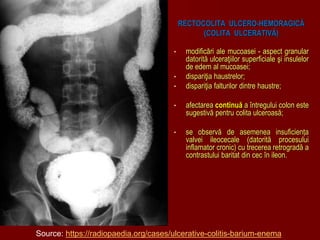

• modificări ale mucoasei - aspect granular

datorită ulceraţiilor superficiale şi insulelor

de edem al mucoasei;

• dispariţia haustrelor;

• dispariţia falturilor dintre haustre;

• afectarea continuă a întregului colon este

sugestivă pentru colita ulceroasă;

• se observă de asemenea insuficiența

valvei ileocecale (datorită procesului

inflamator cronic) cu trecerea retrogradă a

contrastului baritat din cec în ileon.

Source: https://radiopaedia.org/cases/ulcerative-colitis-barium-enema